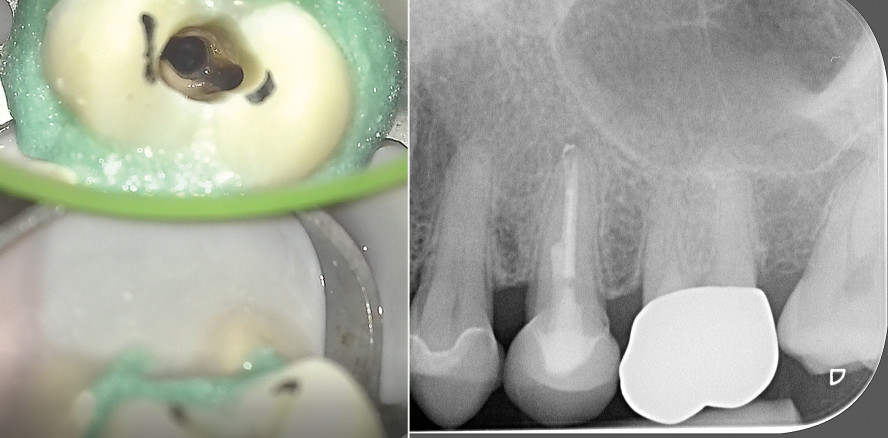

Der röntgenologische Befund zeigte einen intrakanalären Stift (wahrscheinlich Radix-Anker) und eine insuffiziente Wurzelfüllung an Zahn 25 mit apikaler Parodontitis (Abb. 1 und 2). Die Krone an Zahn 25 war stark überstehend. Die Wurzeln der Zähne 23, 24 und 26 zeigten keine apikalen pathologischen Verhältnisse. Zahn 24 zeigte eine Sekundärkaries im distalen Bereich der Kompositfüllung (Abb. 1). Zahn 23 wies eine nicht röntgenopake Kompositfüllung im mesialen Bereich auf. Der Knochenverlauf auf dem Röntgenbild ließ einen leichten horizontalen Abbau erkennen.

Nach der Trepanation und erster ausgiebiger Spülung mit Natriumhypochlorid (5,5 %) war unter dem Mikroskop im palatinalen Bereich eine kleine Öffnung erkennbar (Abb. 3), die mit einem Micro-Opener (Dentsply Sirona) sondiert wurde. Es handelte sich um einen zweiten, palatinalen Kanal, der nicht mit dem bukkalen Kanal in Verbindung stand. Ohne entsprechende optische Vergrößerungshilfen wäre es nicht möglich gewesen, diesen zu erkennen, zumal die Aufsicht auf den bukkalen, schon stark aufbereiteten Kanal zuerst nur einen zentralen Kanal vermuten ließ. Der palatinale Kanal wurde anschließend initial mit der SX Feile des ProTaper® Systems (Dentsply Sirona) erweitert, um anschließend einen Gleitpfad mit K-Feilen ISO 06, 08, 10 und 15 (VDW) anzulegen. Die weitere Aufbereitung erfolgte unter Zuhilfenahme der elektronischen Messlängenbestimmung (VDW.GOLD® RECIPROC®, VDW) mittels ProGlider® (Dentsply Sirona) und ProTaper Next® X1, X2 auf volle Arbeitslänge bzw. ProTaper Next® X3 (alle Dentsply Sirona) 0,5 mm kürzer (Abb. 4–6).

Nach Reinigung der Kanäle und der Pulpakammer mit AH Plus Cleaner wurde die Kavität mit dem Airsonic® Mini Sandblaster (Hager & Werken) und Aluminiumoxidpulver sandgestrahlt. Der postendodontische Verschluss der Zugangskavität erfolgte mit SDR® (Dentsply Sirona) und Tetric White (Ivoclar Vivadent). Auf der Abschlussaufnahme (Abb. 8) zeigt sich, dass durch die damalige Insertion des Radix-Ankers ein großer Defekt im Wurzelkanalsystem gesetzt wurde. Dieser wurde mittels SDR® sehr tief im Kanal verschlossen. Der Zahn wurde für sechs Monate mit dem adhäsiv eingegliederten Provisorium belassen, bevor eine mit dem CEREC-System angefertigte e.max® CAD-Krone eingegliedert wurde.